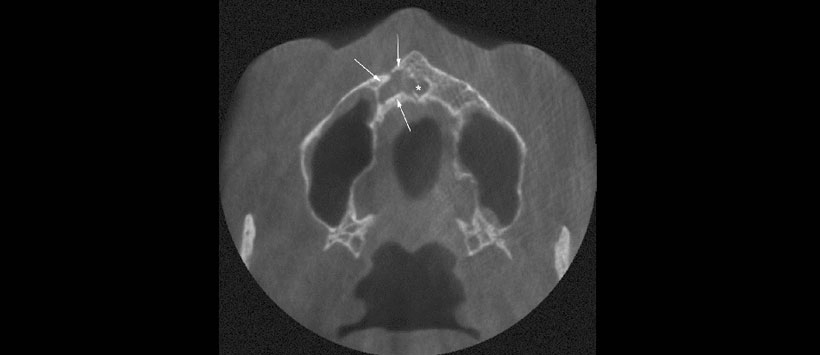

Los resultados mostraron que en el grupo de trauma (n = 96), el 31,3% tenía al menos un incisivo maxilar perdido y el 95,8% tenía incisivos con tratamiento de endodoncia. La dimensión anteroposterior del foramen incisivo (p = 0.02) y del CNP a mitad de camino (p = 0.04) fue significativamente mayor en el grupo de trauma. Significativamente se evidenció más casos con un signo abultado en el grupo de trauma (n = 19) que en el grupo control (n =3, p = 0,001). Se identificó una osteólisis apical en el 5,1% de incisivos, y 12/38 mostraron una fusión con el CNP.

El estudio concluyó que dimensiones más amplias del CNP y un signo abultado puede sugerir una lesión dentoalveolar anterior en el maxilar anterior. La osteólisis periapical del incisivo central de más de 5 mm de diámetro tiende a fusionarse con el CNP.

- Figura 5: Lesión osteolítica de forma irregular (flechas) en la vista axial de una imagen CBCT (Scanora 3D, campo de visión 13 × 14,5 cm, tamaño de vóxel de 0,25 mm), que se ha fusionado con el canal nasopalatino (asterisco)